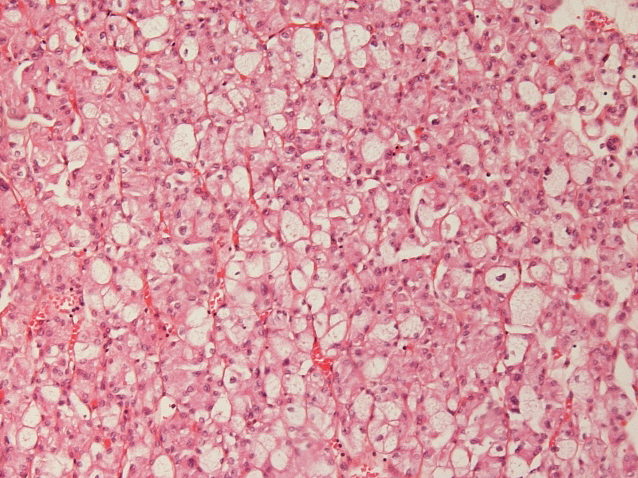

Consensus grade: Chromophobe RCC

H&E not typical of eosinophilic chromophobe. Have seen Hale's positive cases like this that do not have chromosomal abnormilities typical of chromophobe.

another chromophob, I guess very classic, could maybe become a consensus case